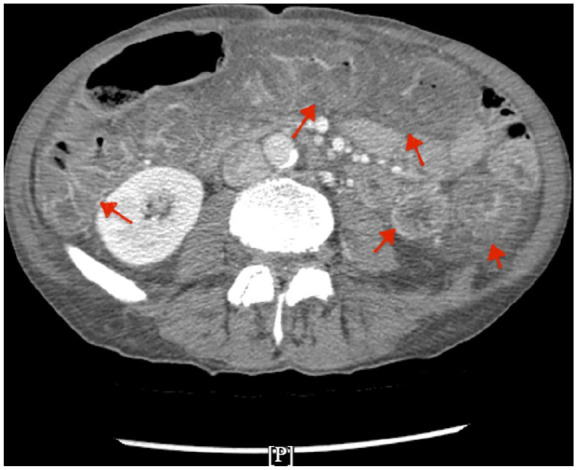

Immunotherapy-induced pseudomembranous colitis (PMC) is an uncommon but increasingly recognized adverse effect of immune checkpoint inhibitors, particularly in patients with advanced malignancies. We present a case of a 68-year-old male with gastric adenocarcinoma undergoing treatment with immunotherapy and chemotherapy, who developed symptoms of PMC. Workup for Clostridium difficile and other common etiologies was negative. Colonoscopy revealed severe mucosal congestion and yellowish-green exudates, consistent with PMC. Based on the biopsy results and clinical presentation, after excluding common etiologies, immunotherapy-induced PMC was suspected. The patient responded to steroid therapy, with gradual improvement and a tapering regimen upon discharge. This case underscores the diagnostic challenges in identifying the etiology of PMC, particularly when it presents with diffuse involvement of the colon, which is an uncommon presentation for immunotherapy-related colitis. The overlap in clinical, endoscopic, and histopathological findings with other forms of colitis, such as Clostridium difficile infection (CDI) and inflammatory bowel disease, highlights the need for heightened awareness among clinicians. This case highlights the diagnostic challenges in recognizing immunotherapy-induced PMC, particularly with atypical, diffuse colonic involvement. The overlapping features with other colitis make timely diagnosis difficult. Further research is needed to refine diagnostic criteria and management strategies for immunotherapy induced colitis (IMC).

Abstract Image